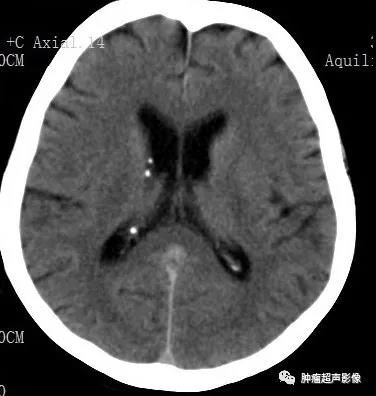

女,61,因肾肿瘤入院治疗,超声及CT示两肾多发错构瘤,建议头颅检查。

头颅CT示两侧侧脑室下多发小结节状钙化,增强MR示室管膜下结节明显强化。